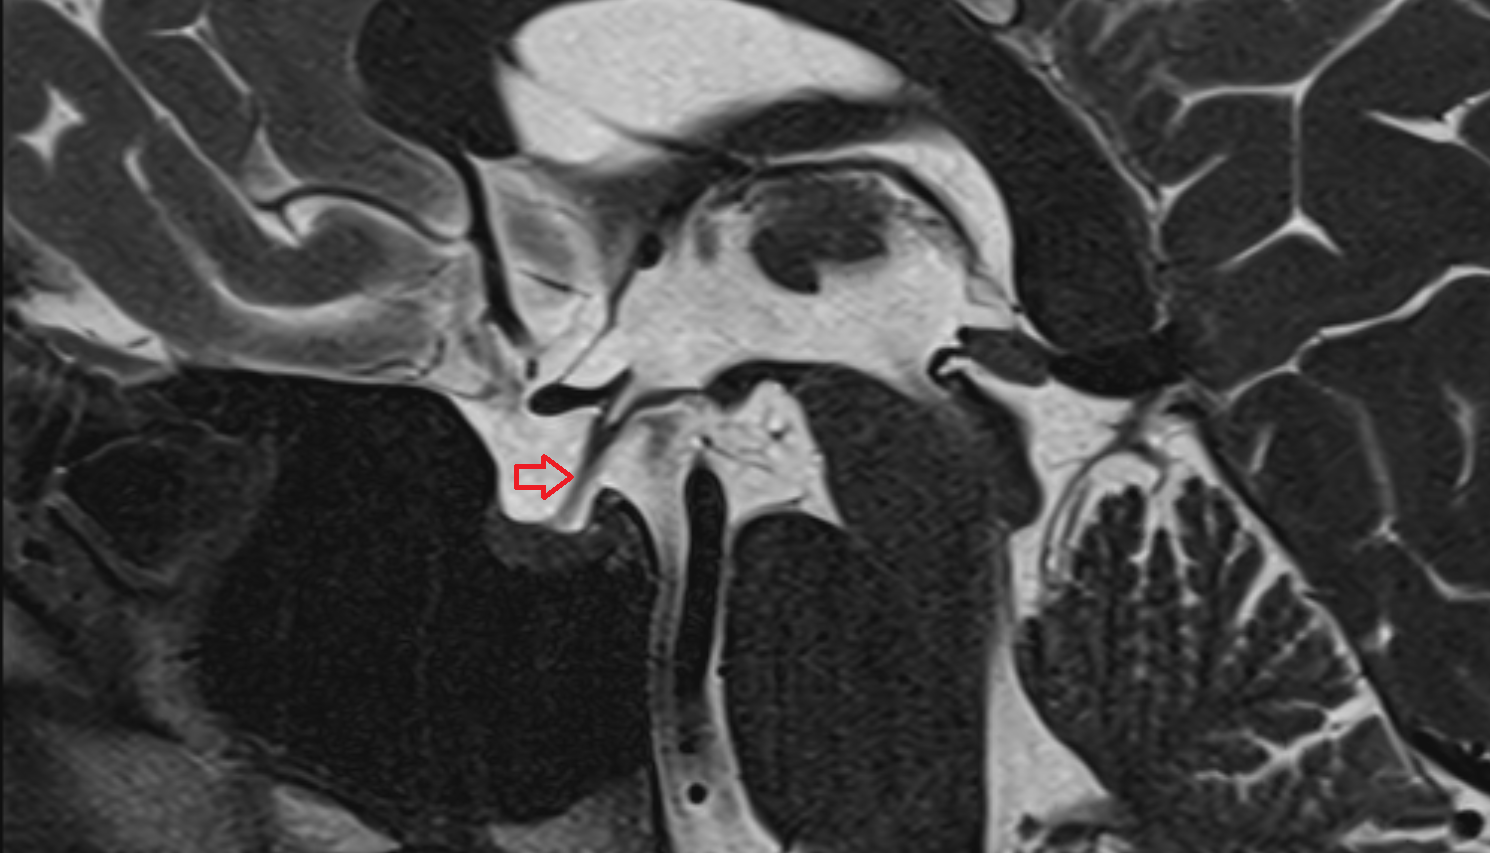

- Median aperture of fourth ventricle (foramen of Magendie)